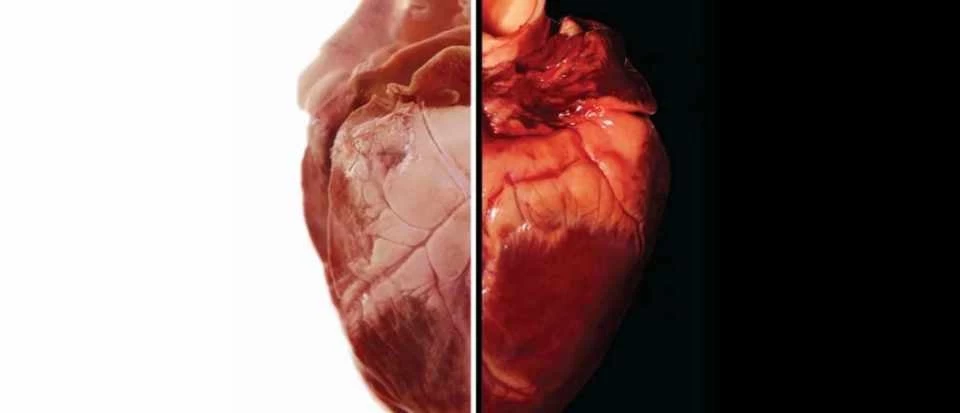

Προ των πυλών οι μεταμοσχεύσεις καρδιάς από χοίρους σε ανθρώπους;

Οι γενετικά τροποποιημένες καρδιές χοίρων θα μπορούν να χρησιμοποιηθούν για μεταμοσχεύσεις σε ανθρώπους μέσα σε μόλις τρία χρόνια, σύμφωνα με τον πρωτοπόρο χειρουργό που πραγματοποίησε τ...